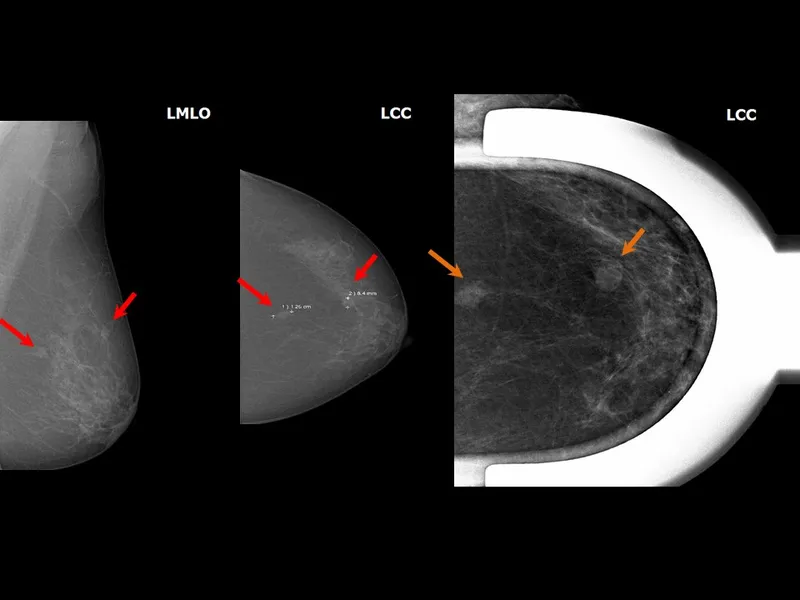

Standard Projections - Two-Angle Truth

- Two views/breast for 3D localization.

- 1. Craniocaudal (CC) View:

- Beam: Superior → Inferior.

- Shows: Medial vs. Lateral position.

- Adequacy: Pectoral muscle (~30%); PNL visualized.

- 2. Mediolateral Oblique (MLO) View:

- Beam: Medial → Lateral, angled 45-60°.

- Shows: Superior vs. Inferior position; most tissue.

⭐ In an adequate MLO view, the pectoral muscle should be visible to the level of the posterior nipple line (PNL) or deeper.

- Adequacy: Inframammary fold (IMF) open.

- "Two-Angle Truth": Differentiates lesions vs. superimposition.